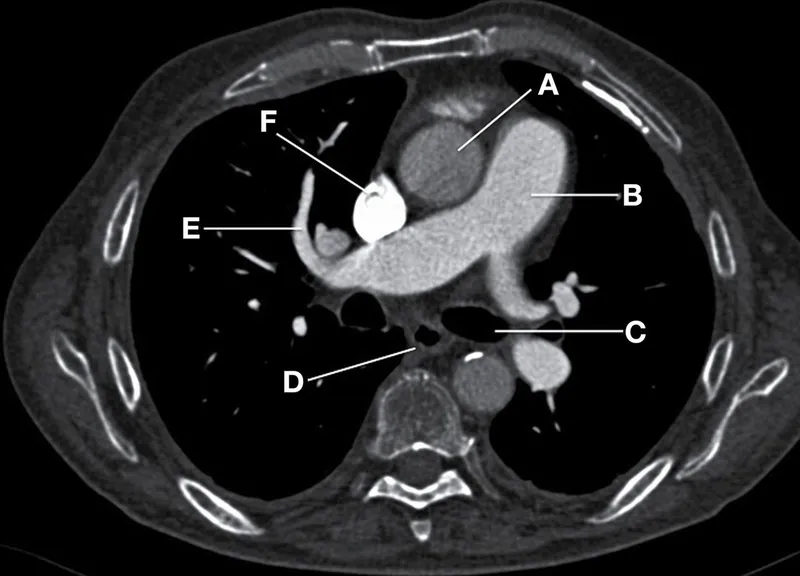

CT Anatomy - Chest Checkpoints

- Key Mediastinal Structures (Cranial to Caudal Scan):

- Vessels: SVC, IVC, Aorta (ascending, arch with branches, descending), Pulmonary Artery (main, R/L branches).